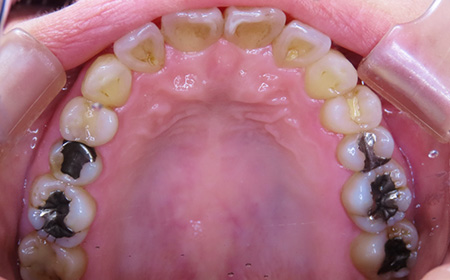

CASE01

Before

After